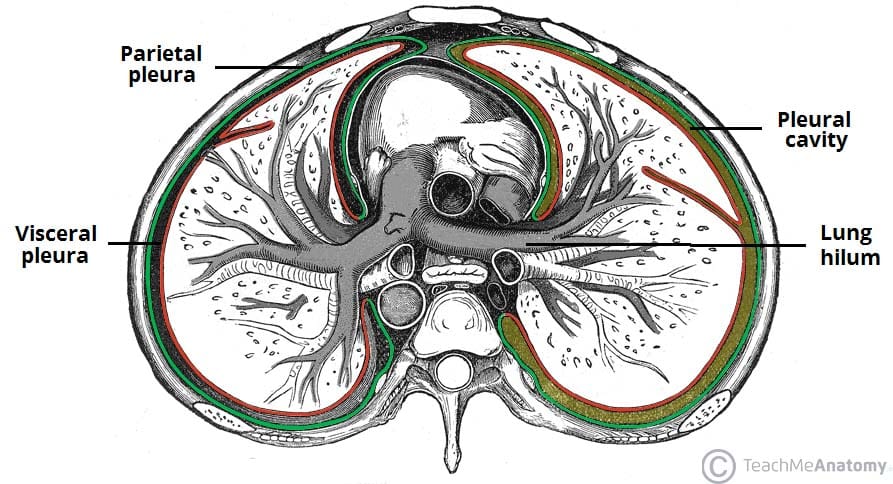

Fig 1.1 - The parietal and viscera pleura, and the pleural cavity. Note how the two layers of pleura are continuous at the hilum of the lung.

The parietal and viscera pleura, and the pleural cavity. Note how the two layers of pleura are continuous at the hilum of the lung.

There are two pleurae in the body: one associated with each lung. They consist of a serous membrane – a layer of simple squamous cells supported by connective tissue. This simple squamous epithelial layer is also known as the mesothelium.

Each pleura can be divided into two parts:

• Visceral pleura – covers the lungs.

• Parietal pleura – covers the internal surface of the thoracic cavity.

These two parts are continuous with each other at the hilum of each lung. There is a potential space between the viscera and parietal pleura, known as the pleural cavity.